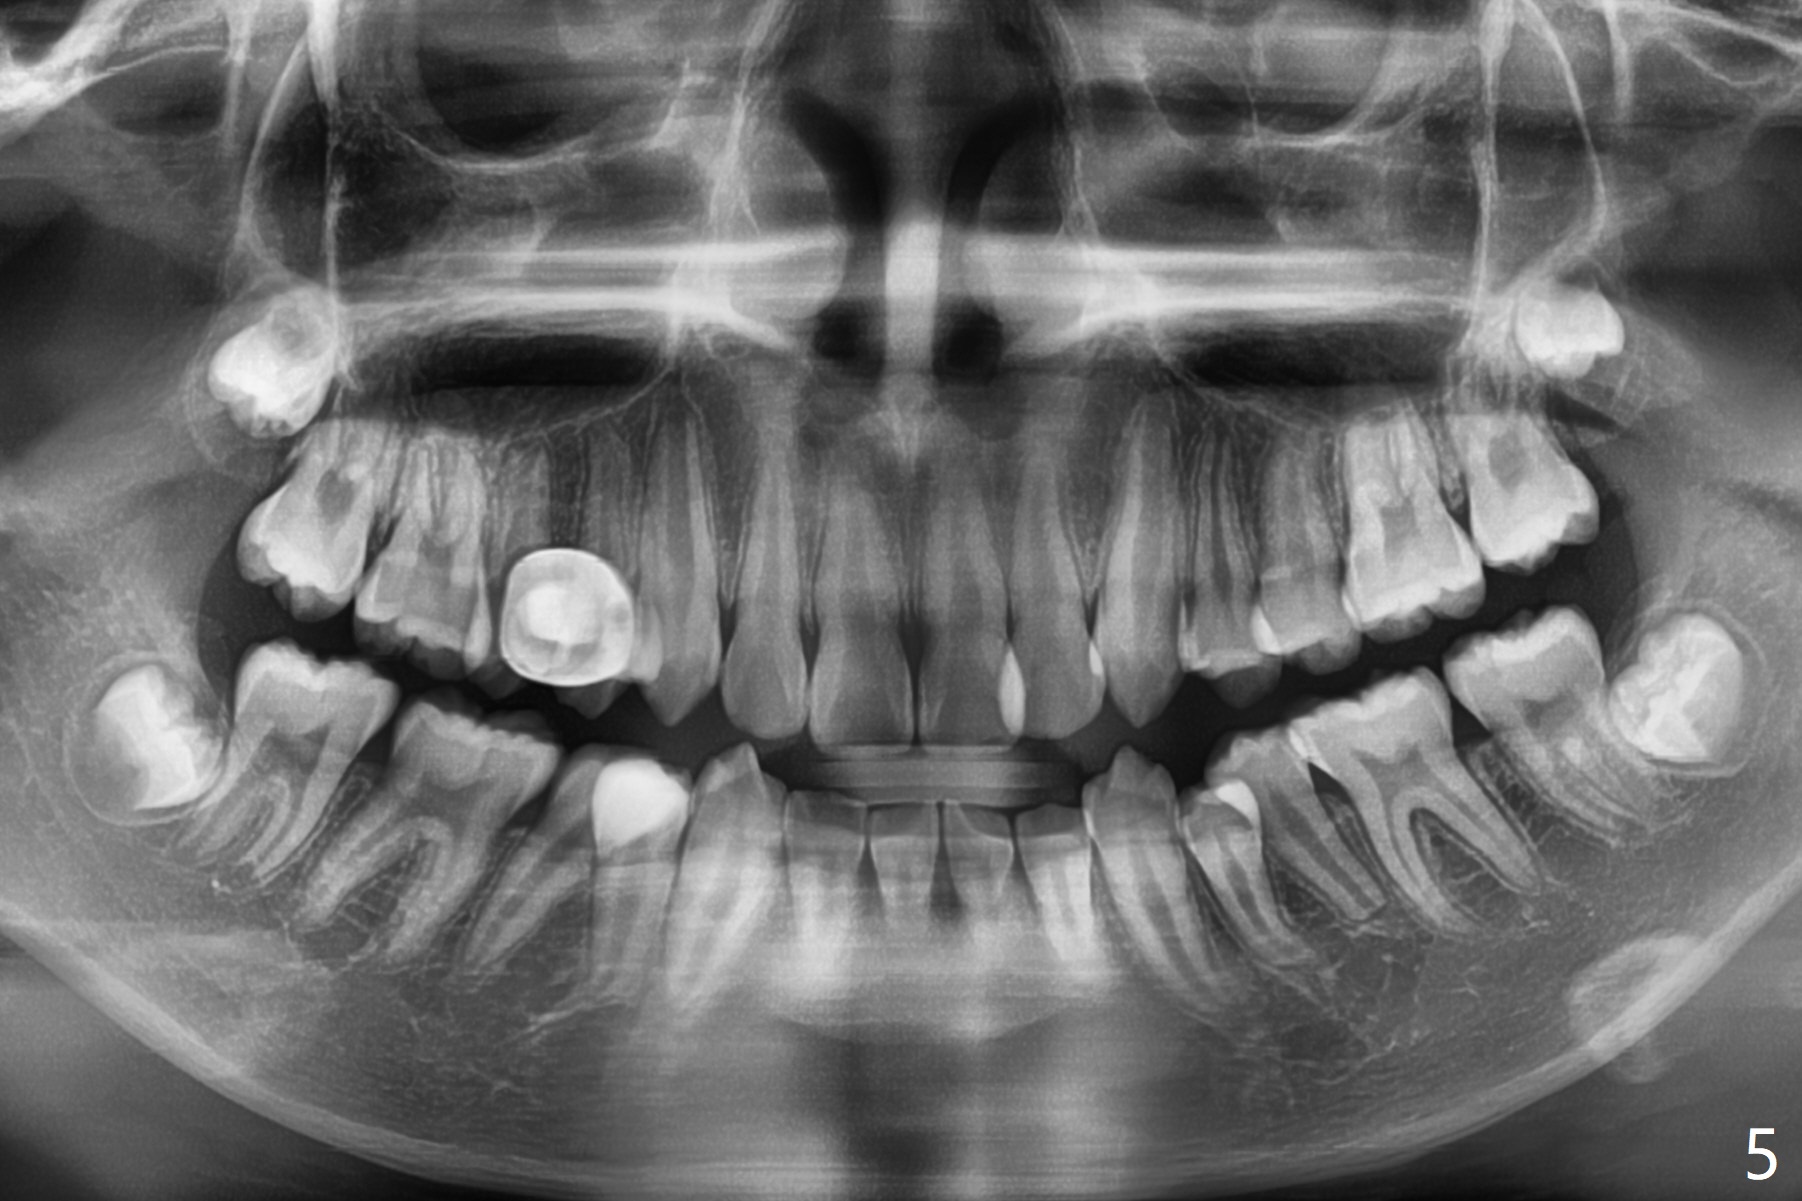

A 13-year-old man has protrusive lips (Fig.1,3,4) with upper midline deviation to the left (Fig.2).  Crowding is severe with LR5 severe lingual inclination (Fig.5,6,10).  To facilitate L6s' uprighting (Fig.10), LR5 and 3 of the 1st bicuspids will be extracted (Fig.6-8 x or *) and molar bands with lingual cleats will be used for the lower.  Cross arch molar retraction will be initiated immediately.  Open coil spring will be placed between UL1 and 3 with the 1st wires to correct the upper midline deviation and to gain the space for UL2.

Criteria for extraction:

1) Facial esthetics: looked 'full' and would worsen with non extraction tx/advancement of anterior teeth.

2) Dental open bite

3) U incisor proclination